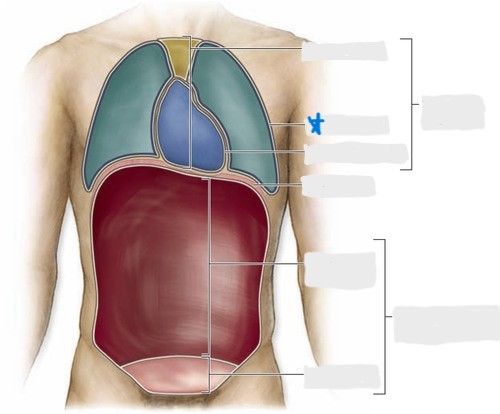

pleural cavity

pericardial cavity

mediastinum

abdominal cavity

pelvic cavity